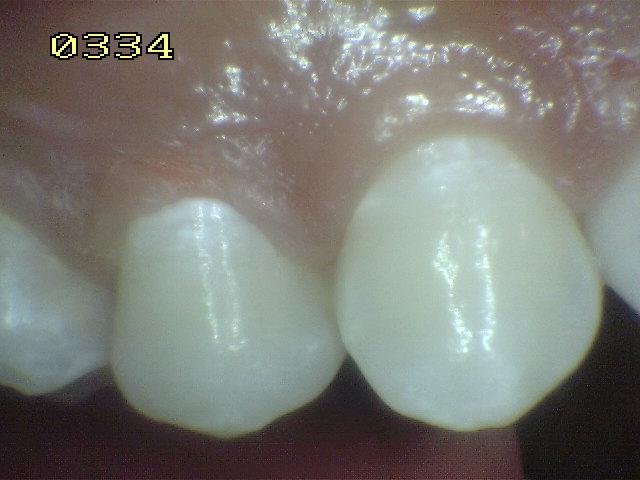

Las manchas opacas por fluorosis leve deben

diferenciarse con los códigos1 y 2 de ICDAS. En las

fluorosis el esmalte aparece brillante; mientras que

en el proceso de caries se observa un blanco aspecto

de tiza. (sin brillo) |